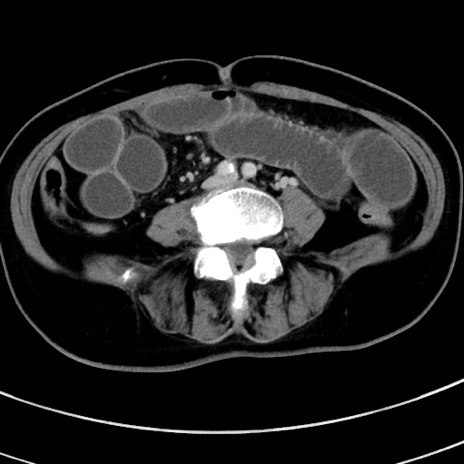

冠状断像

【症例】 60歳代女性

【主訴】むかつき、みぞおちの痛み

【現病歴】3日前よりむかつきがあり、食事がとれない。

【既往歴】糖尿病

【身体所見】発熱なし、心窩部圧痛軽度あるも、腹膜刺激症状なし。

【データ】WBC 7400、CRP 1.92